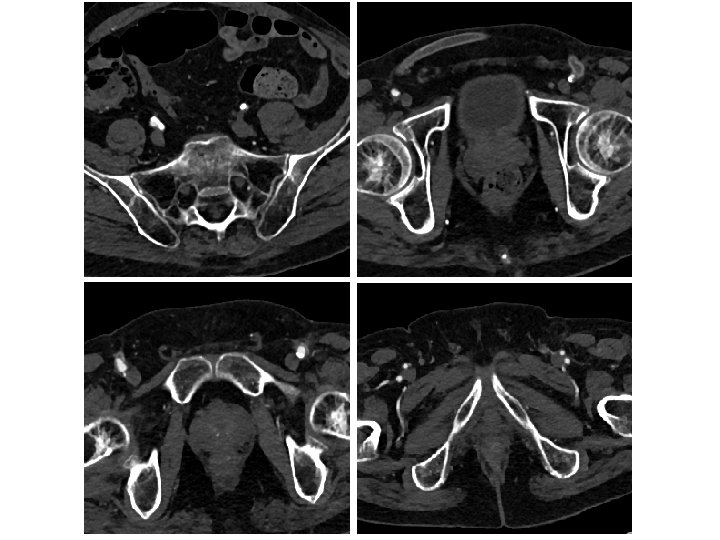

SE Stent Compression Is A Problem • 53 patients (28 females) prospective aorto-iliac stent • 165 aorto-iliac stents placed with CBCT confirmation • 20/53 patients underwent adjunctive procedures after the primary stenting • In 24. 5% (13/53) cases, adjunctive procedures were indicated solely on the CBCT findings • 26 of the 53 patients had kissing stents placed at the aortic bifurcation • Of the kissing stent patients, 34. 6% required adjunctive procedures and in two thirds these stent compressions were detected only by CBCT. Törnqvist P, et al. Utility of Intra-operative Cone Beam Computed Tomography in Endovascular Treatment of Aorto-iliac Occlusive Disease. Eur J Vasc Endovasc Surg. 2015

Kissing SE Stents Often Asymmetric Subgroup analysis between the types of stents used and adjunctive procedure showed that self expandable stents were more prone to need adjunctive procedure in the common iliac artery (p =. 048) Törnqvist P, et al. Utility of Intra-operative Cone Beam Computed Tomography in Endovascular Treatment of Aorto-iliac Occlusive Disease. Eur J Vasc Endovasc Surg. 2015